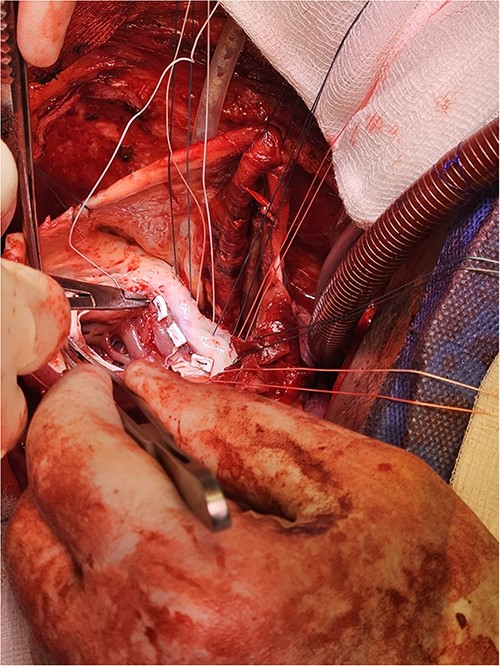

Following median sternotomy, cardiopulmonary bypass was instituted (bicaval drainage, ascending aortic return). Antegrade cardioplegia was delivered with aortic root venting and bicaval snaring. Dense adhesions surrounded the aneurysm, which had a thin wall, measured ⁓15 cm from LV apex to mitral annulus, and contained around 150 g of clot. The posterior mitral leaflet appeared retracted, preventing coaptation due to LV stretching. The aneurysm was resected (Fig. 2), and the LV wall repaired with a 5 × 3 cm patch, restoring normal LV size (Fig. 3). The musculotendinous junctions of the anterior and posterior papillary muscles were approximated using pledgeted 3–0 polypropylene sutures (Fig. 4). The patch repair was completed (Fig. 5), and the overlying sac oversewn for haemostasis.

The LV aneurysm was resected down to its neck into healthy ventricular scar tissue. The posterior chordae can be seen from the ventricular defect.